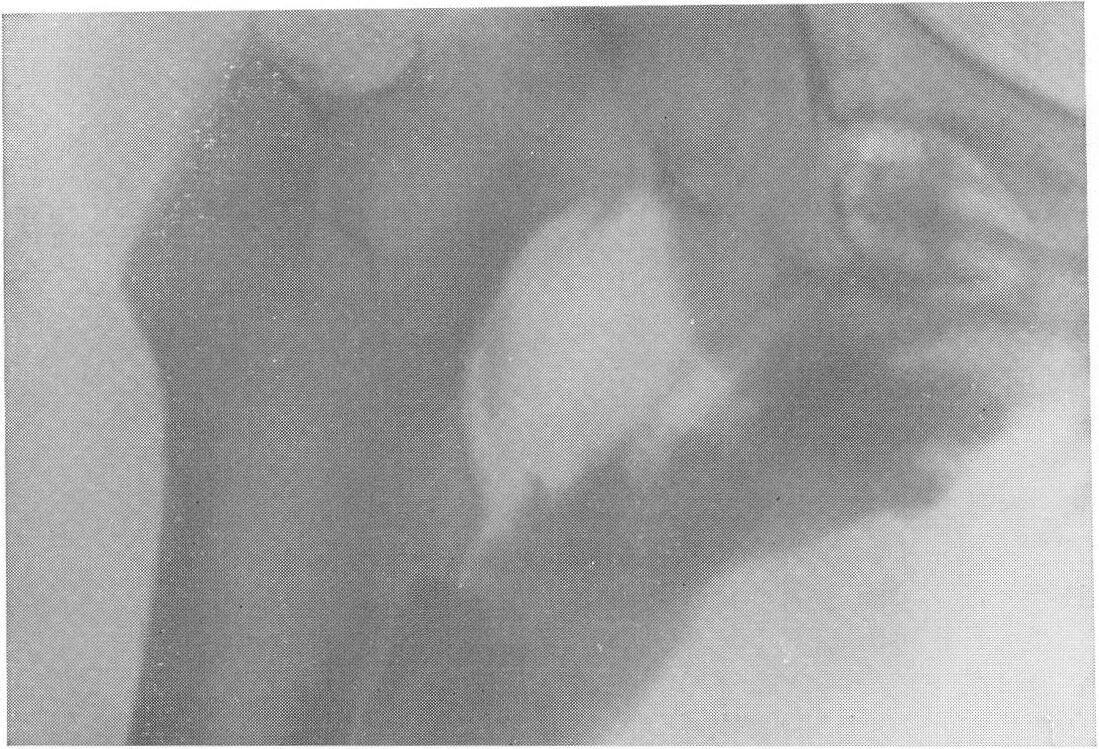

Оссифицированный миозит